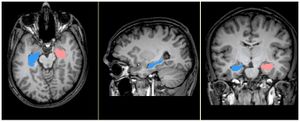

- 4.29 BNST Neurocircuitry in Humans